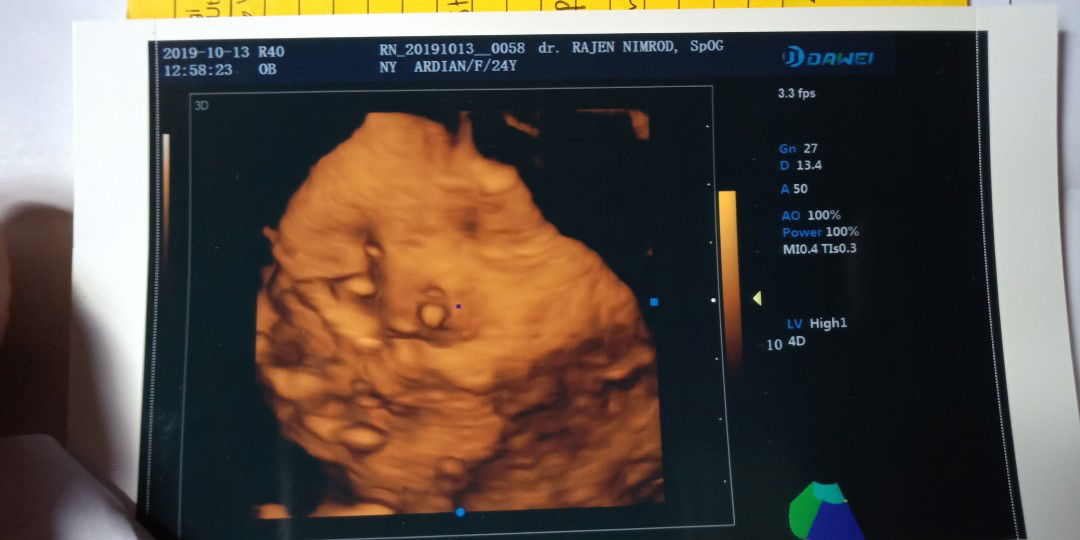

Ada yg tau kah ini cwe atau cwo?

Ini muka bund?

7bulan